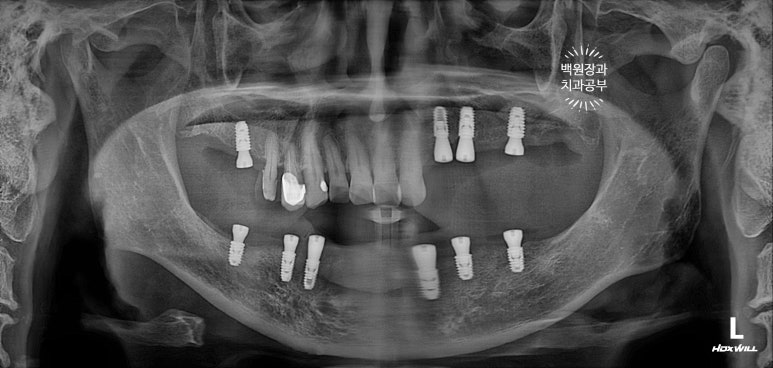

확인하실 수 있듯, 아래턱의 경우 단 6개의 임플란트만 심었음에도 불구하고, 총 12개의 치아를 만들어드릴 수 있었습니다. 위턱의 경우 좌측 3개, 우측 1개의 임플란트로 총 5개의 치아를 만들어드린 상태입니다.

치과용 파노라마를 촬영하여 뼈 속의 임플란트 고정체와 제작한 맞춤형 지대주 (custom abutment)가 잘 연결되어있는지 확인할 수 있었습니다. 아직 임시치아이기에 엑스레이에서는 마치 없는 것처럼 흐릿하게 보이네요.

치료가 마무리된 후의 치과용 파노라마 사진입니다.

정~~~말 깔끔하게 마무리가 잘 되었네요!!!

치료 전 후 비교로 가장 명확히 볼 수 있는 사진이 치과용 파노라마 사진입니다.

엑스레이에서 보이진 않지만, 아래턱 전체틀니는 이제 사용하지 않아도 되시게 되었고,

만성 치주염으로 흔들리던 위턱의 임플란트들도 깔끔하게 임플란트로 대체되었습니다.